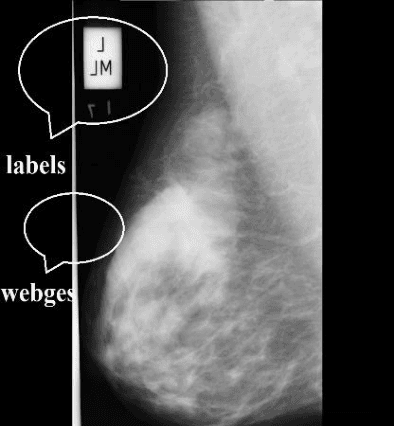

Abstract:Digital mammogram inspection is the most popular technique for early detection of abnormalities in human breast tissue. When mammograms are analyzed through a computational method, the presence of the pectoral muscle might affect the results of breast lesions detection. This problem is particularly evident in the mediolateral oblique view (MLO), where pectoral muscle occupies a large part of the mammography. Therefore, identifying and eliminating the pectoral muscle are essential steps for improving the automatic discrimination of breast tissue. In this paper, we propose an approach based on anatomical features to tackle this problem. Our method consists of two steps: (1) a process to remove the noisy elements such as labels, markers, scratches and wedges, and (2) application of an intensity transformation based on the Beta distribution. The novel methodology is tested with 322 digital mammograms from the Mammographic Image Analysis Society (mini-MIAS) database and with a set of 84 mammograms for which the area normalized error was previously calculated. The results show a very good performance of the method.